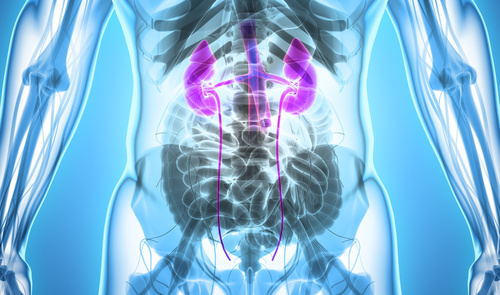

⑥立位で腎臓を使う腰痛治療法

⑨腎臓FCRで立位での腰痛治療

ドヤ顔が出来る腎臓FCRメソッド

腰痛治療に欠かせないのが腎臓のテクニックです。腎臓は大腰筋とも連結があるため腰痛治療において極めて重要です。なのであなたが、腎臓のリリースが出来るようになれば、腰痛患者に驚くべき結果を出すことが出来るようになるのも夢ではありません。

とはいえ、腎臓をリリースするのは、手の感覚が重要ですし、緩む感覚がわからなけらば上手く腰痛治療に活用する事が出来できずにいます。そこで、、、

このセッションでは、姿勢も問わず、手の感覚を必要としない腎臓FCRメソッドの秘密を公開します。例えば、、、

- なぜ、腎臓FCRメソッドは頭蓋骨の動きまでをも改善するのか?

- 腰痛改善率97%、驚異の腎臓FCRメソッド。

- 立ったまま腰痛を治してドヤ顔したい?なら腎臓FCRメソッドを使って下さい。

- 短時間で治療を終えることが、なぜ患者のためになるのか?一度の治療で大腰筋、側頭骨、一時呼吸までをも調整する腎臓FCRメソッドの使い方。